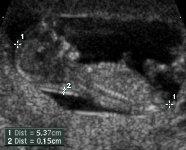

ultralydsundersøgelseDen rutinemæssige 12 ugers ultralydsundersøgelse foretages mellem den 10. og 14. uge (gestationsuge). Gennem undersøgelsen ses fosteret via abdominal ultralyd. Ind imellem er udsigten ikke klar, og det kan derfor blive nødvendigt at foretage en vaginal scanning. Ved den første trimester scanning vil det blive bekræftet at fosteret er i live, og man vurderer gestationsalderen ved at måle krone-hale længde, og ser samtidig efter om der er problemer.

Krone til Hale (CRL) længden er en almen anerkendt måling, som er meget nyttig til måling tidligt i graviditeten. CRL (se billedet til højre, mellem de to hvide markeringer + mærket 1) giver en meget reproducerbar oversigt, og giver den absolutte bedste og mest præcise måling af gestationsalderen. Føtale vækstdiagrammer er blevet specielt udviklede til dette formål, men nogle enkle tommelfingerregler kan også bruges effektivt. Fra den 6. til den 11. svangerskabsuge, vokser den føtale reference med en hastighed omkring 1 mm. om dagen.

Efter 12 uger mindskes nøjagtigheden af CRL gestationsalder beregningen, og erstattes derfor af BPD (biparietal diameter) hvor der foretages breddemåling af det føtale hoved.

Hvad er nakkestivhed Uigennemsigtigheden?

Nakkestivhed Uigennemsigtighed (beskrives også som nakkestivhed gennemskinnelighed) er en samling væsker under fostrets hud i fosterets nakkeregion, (se billedet ovenfor mellem de to hvide + mærker 2), og dette er til stede i alle fostre og ses tidlig i graviditeten.   Væskesamlingen stiger imidlertid gennem graviditeten i mange fostre med Downs syndrom og mange andre kromosomafvigelser. Den mest præcise non invasive test til påvisning af Downs syndrom under graviditeten, er målingen af Nakkestivhed Gennemskinnelighed med ultralyd, mellem den 11. og 14. graviditetsuge.